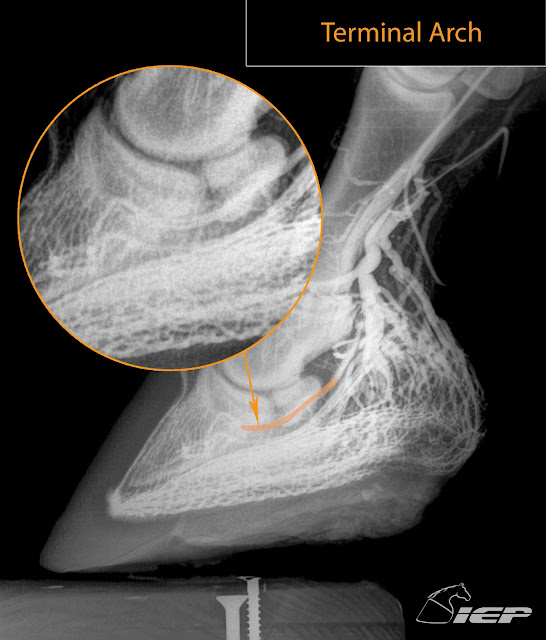

Images below are of a hoof with healthy soft tissue parameters and I would consider to have a healthy venogram. I think the venogram has much to teach us when used in conjunction with evaluation of mechanical forces and load induced vascular compromise. Consider the areas of excessive load, degree of deep digital tendon tension, bone load, heel load, growth rings, soft tissue parameters and how it would relate to or affect the vascular pattern. Just like when you press your fingernail and the pressure forces blood to leave so does load without unload create areas of poor circulation and subsequent poor quality foot mass in the area compromise. What do you think would happen if you placed a clothes pin on the tip of your finger compressing the nail bed and vascular supply in that area? It is fine as long as it is removed in timely fashion but leave it for days and damage will occur. Imagine having this vascular compromise for months as with crushed heels or laminitis. For every pathological foot problem consider performing a venogram and relating the load induced vascular compromise to the seat of pain and external hoof growth ring characteristics. Diminished blood flow equals diminished growth, hence growth rings wider at heel than at toe in a chronic laminitis and more toe than heel in low palmar angles/crushed heel.

Food for thought.